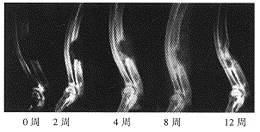

图1实验组术后各期X线表现

, 百拇医药 本实验的X线片特点为实验组新骨形成为自骨缺损两断端及靠近桡骨侧逐渐向中心生长,基本上呈现为“包围”式生长方式。对照组这种现象不明显(图1~3)。按Yasko骨缺损修复分期方法[6],0期:无新骨形成;1期:新骨占骨缺损的百分比<25%;2期:25%~49%:3期:50%~74%;4期:75%~99%;5期:全部被新骨替代。本实验各组不同时相骨缺损修复的X线表现结果见表1。